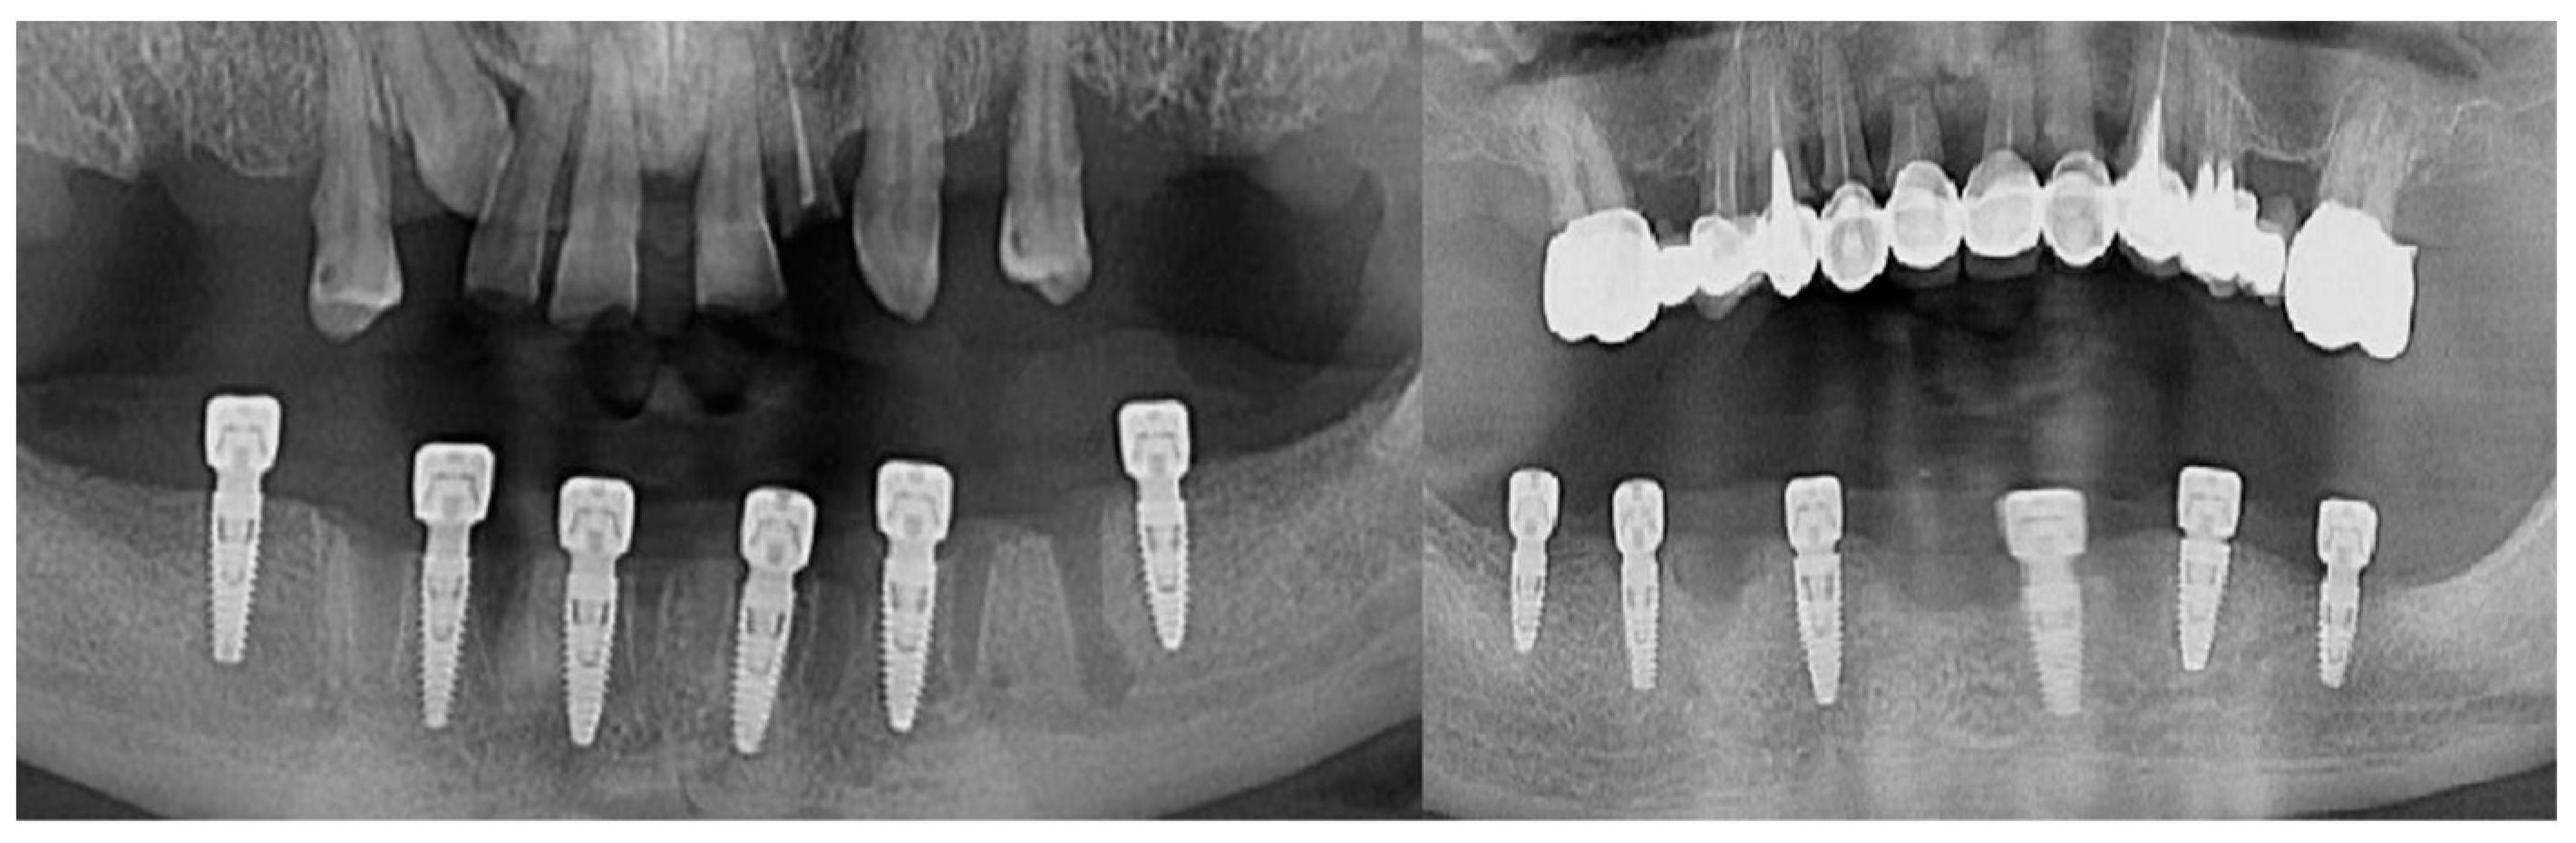

The follow-up of the patients was made at 1 month, 3 months, and 6 months from the moment the suture threads were removed. Retro-alveolar and OPG X-rays were performed in isometric and orthoradial incidences using the Belot method [16] (Figure 3). In cases where any kind of suppurated complications occurred less than a month after the insertion, the dental implant was removed.

Figure 3.

Radiological images of clinical cases during the follow-up period.